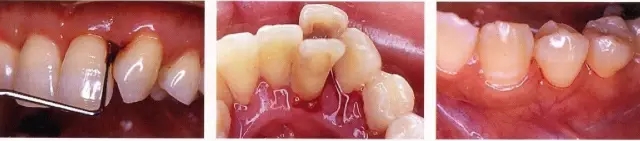

例:確認到不合適的修補物和垂直的骨缺損的時候

一定要記錄好!探診時出血

有出血量大的時候,也有出血量非常少的時候,無論哪一種都是炎癥出現(xiàn)的標志,要確認原因后進行對應。